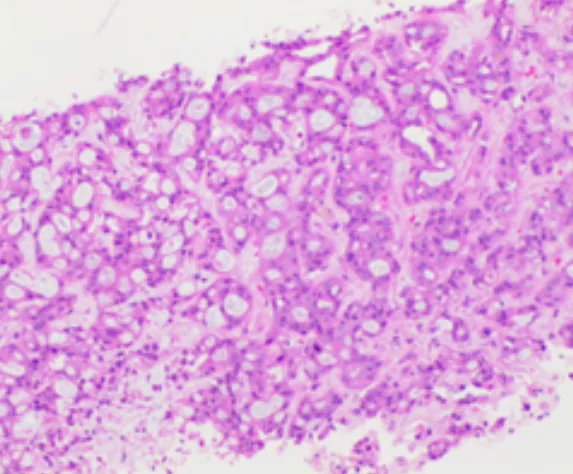

肝內病灶穿刺組織病理結果

(肝內病灶穿刺組織)肝組織內見腺癌浸潤,免疫組化結果:CK7(+),CK19(+),Ki-67(約30%+),P53(彌漫強+),CEA(部分+),TTF-1(-),結合病史及影像學檢查,首先考慮胰腺癌轉移。